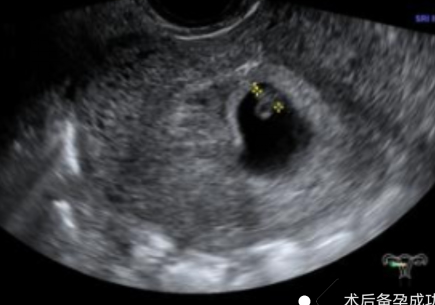

幾個(gè)月前,陳女士(化名)突發(fā)不規(guī)則陰道出血癥狀,且出血持續(xù)多天未見(jiàn)緩解,身體不適與生育焦慮雙重壓力下,前往我院就診,尋求專業(yè)診療方案。不規(guī)則陰道出血是婦科臨床的高頻癥狀,其背后病因復(fù)雜,可能潛藏著子宮內(nèi)膜息肉、黏膜下肌瘤、子宮內(nèi)膜增生等多種病變。若未能及時(shí)明確診斷并采取干預(yù)措施,不僅會(huì)嚴(yán)重影響患者日常生活質(zhì)量,更可能對(duì)生育功能造成不可逆的潛在威脅。針對(duì)該患者的病情,婦科胡菊英副主任帶領(lǐng)婦科團(tuán)隊(duì)展開(kāi)全面評(píng)估,最終確定宮腔鏡手術(shù)為最佳診療方案。該技術(shù)無(wú)需開(kāi)刀,可經(jīng)人體自然腔道進(jìn)入2025-11-10